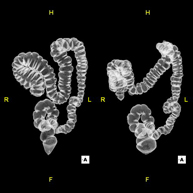

- Colonoscopia virtual

La colonoscopia virtual es una técnica no invasiva que permite la visualización tridimensional y bidimensional del intestino grueso o del colon mediante la toma secuencial de imágenes captadas con TC Multidetector de última generación. La calidad de las imágenes permite la navegación virtual por el interior del recto y del colon gracias al procesamiento en estaciones de trabajo especializadas. La preparación de la prueba consiste en realizar una dieta baja en fibra tres días antes de la prueba (para limpiar el colon y el recto) y de la ingestión de contraste oral yodado el día antes de la prueba (para marcar las heces y poder distinguirlas correctamente de las posibles lesiones colónicas). A diferencia de la fibrocolonoscopia, no se requiere sedación ni soluciones evacuantes. La prueba se realiza en la sala del TC donde, a través de un pequeño tubo flexible, se insufla aire para distender el colon.